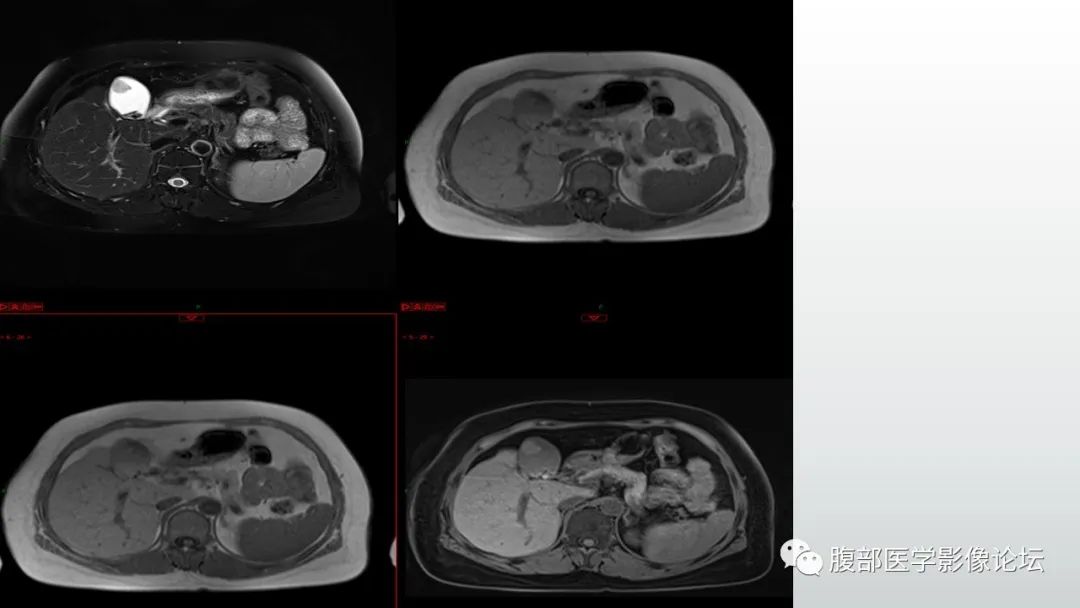

【病例】胆囊管状腺瘤1例CT及MR影像表现-3